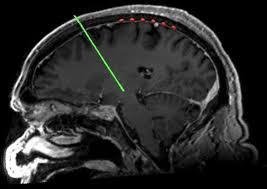

이러한 증상들은 우리 뇌의 '흑질'이라는 부위에서 도파민이라는 신경전달물질을 만드는 세포가 점차 줄어들면서 발생합니다. 도파민은 우리 몸의 움직임을 부드럽고 정교하게 조절하는 데 필수적인 역할을 합니다.

파킨슨병 진단은 혈액 검사나 MRI 한 번으로 확정되지 않습니다. 주로 신경과 전문의가 환자의 병력 청취, 신경학적 검진을 통해 위에서 언급한 특징적인 증상들을 확인하여 임상적으로 진단합니다.

필요한 경우, 뇌의 도파민 운반체 상태를 확인하는 'DAT-PET'이나 'DAT-Scan' 같은 영상 검사를 보조적으로 사용하여 정확한 파킨슨병 초기증상을 감별하기도 합니다.